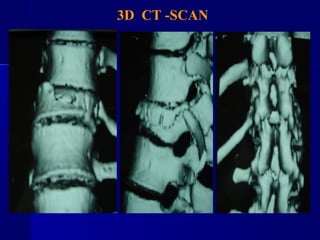

3D CT -SCAN